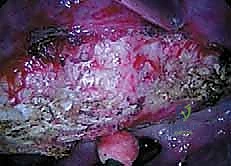

هذه العملية هي تحفة فنية هندسية وطبية. إليكم كيف يقوم الأستاذ الدكتور محمد هطيف وفريقه الجراحي المتميز بتنفيذها خطوة بخطوة في أفضل مستشفيات صنعاء المجهزة.

الخطوة 1: التخدير وتحديد الوضعية (Positioning)

يتلقى المريض تخديراً عاماً. يتم وضع المريض على جانبه (Lateral Decubitus Position) على طاولة عمليات خاصة تسمح باختراق الأشعة السينية. يتم تثبيت المريض بدقة شديدة لضمان عدم تحركه أثناء الإجراء.

الخطوة 2: المراقبة العصبية الفسيولوجية (Neuromonitoring)

هذه خطوة حاسمة لضمان الأمان. يتم توصيل أقطاب كهربائية بجسم المريض لمراقبة وظائف الحبل الشوكي والأعصاب بشكل لحظي (Real-time) طوال فترة الجراحة. أي تغيير في الإشارات العصبية ينبه الجراح فوراً، مما يجعل خطر الشلل شبه معدوم.